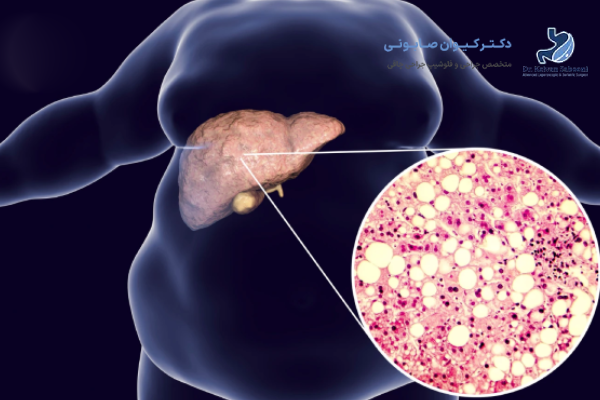

کبد چرب غیرالکلی (NAFLD) به شرایطی گفته میشود که در آن بیش از 5 تا 10 درصد وزن کبد از چربی تشکیل شده باشد. علت اصلی آن اغلب سبک زندگی ناسالم، پرخوری، مصرف غذاهای پرچرب و قند بالا، همراه با کم تحرکی است.

عوامل خطر اصلی شامل چاقی، دیابت نوع 2، فشار خون بالا و کلسترول بالا هستند. این بیماری به تدریج پیشرفت میکند و در صورت عدم درمان، احتمال بروز عوارض جدی کبدی وجود دارد.

چاقی به عنوان مهمترین عامل ابتلا به کبد چرب شناخته میشود. در افراد دارای شاخص توده بدنی بالا (BMI>30)، احتمال تجمع چربی در کبد بسیار بیشتر است. سلول های چربی اضافی نه تنها در زیر پوست، بلکه در اطراف اندام های داخلی از جمله کبد رسوب میکنند. این تجمع چربی، مقاومت به انسولین را افزایش داده و سبب اختلال در متابولیسم قند و چربی میشود.

کبد چرب در صورت پیشرفت میتواند منجر به فیبروز، سیروز و حتی سرطان کبد شود. تحقیقات نشان داده اند که جراحی لاغری با کاهش چربی و التهاب کبد، احتمال پیشرفت بیماری را به میزان زیادی کاهش میدهد. به همین دلیل، این روش نه تنها درمانی برای کبد چرب است بلکه نقش پیشگیرانه نیز ایفا میکند.